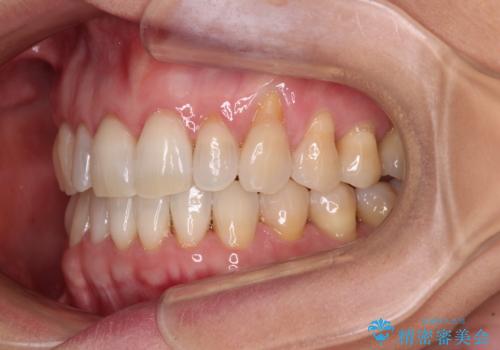

- 前歯の上下スペースによる食べにくさを気にして来院された患者様です。

インビザラインにより上下の前歯の隙間を閉じていくこととしました。

舌の突出癖があると上下前歯にスペースが開くため、矯正治療を機会に舌癖を改善するトレーニングを行ってもらい、矯正治療後の後戻りを防止するように指導しています。